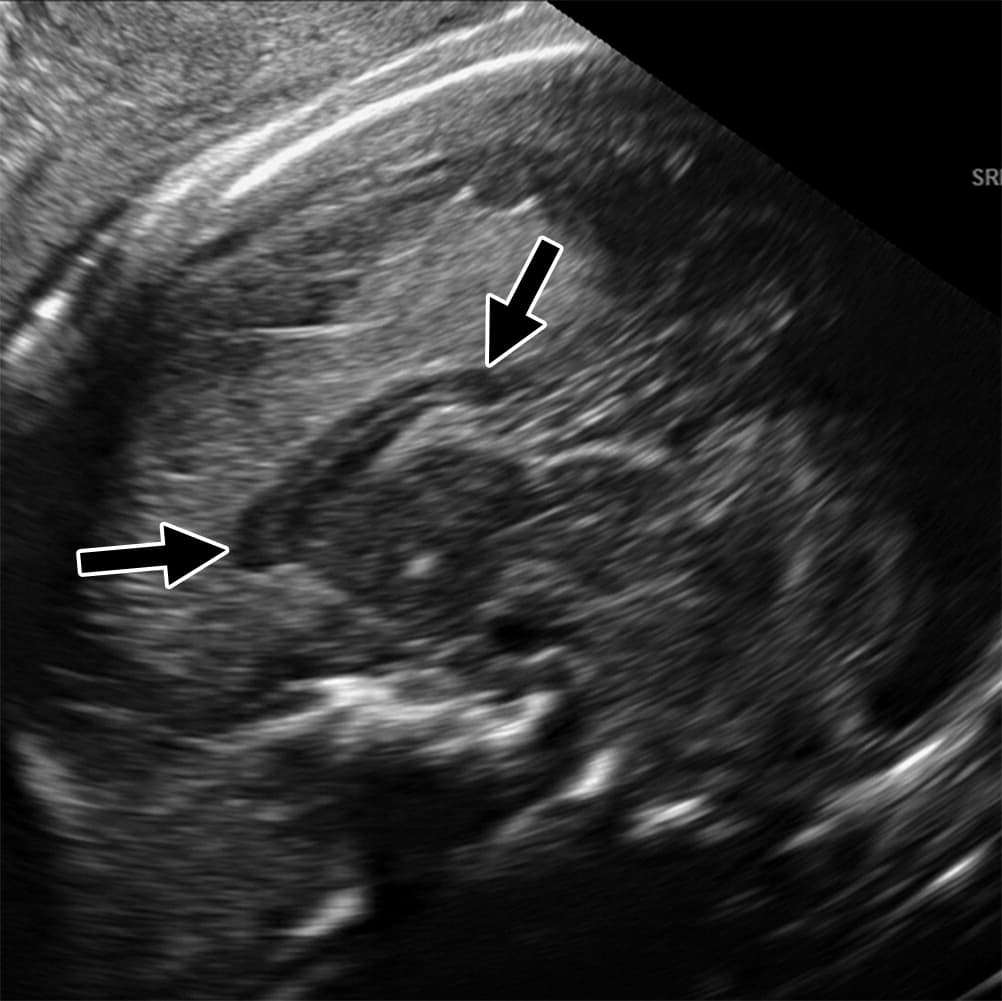

Investigadores brasileños difundieron este martes el mayor número hasta ahora disponible de imágenes computarizadas, resonancias magnéticas y ultrasonidos, de bebés y fetos infectados con el virus del Zika. El daño es mucho mayor del que anticipaban.

Así describe la radióloga brasileña Fernanda Tovar-Moll lo que vio al analizar centenares de imágenes computarizadas, resonancias magnéticas y ultrasonidos de 45 bebés que se contagiaron de zika en el vientre materno en el estado de Paraíba, en el noreste del país, donde el brote ha sido severo.

La mayoría nació con microcefalia, cuya característica más llamativa es que tienen el cerebro y la cabeza más pequeña. Pero muchos sufren una escala y severidad de daño mucho peor en partes importantes del cerebro como el cuerpo calloso, que conecta los dos hemisferios; el cerebelo, que juega un papel significativo en el movimiento, equilibrio y habla; y los ganglios basales, que controlan el pensamiento y la emoción.

Todavía se desconoce exactamente cómo el zika logra penetrar la placenta y contagiar al feto, cuando la mayoría de los víruses no lo consigue. Tampoco el por qué solo algunas mujeres embarazadas que están infectadas de zika transmiten el virus a su feto. Pero se cree que el daño mayor ocurre durante el primer trimestre. “A las 20-24 semanas ya se pueden ver la mayoría de las anomalías en un ultrasonido”, comentó Tovar-Moll.